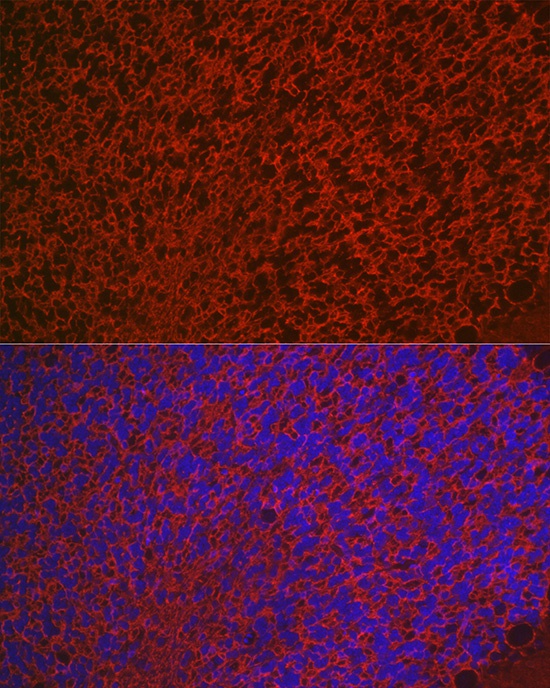

Immunofluorescence analysis of paraffin-embedded rat brain using Aquaporin-4 (AQP4) Rabbit pAb (CAB2887) at dilution of 1:50 (40x lens). Secondary antibody: Cy3-conjugated Goat anti-Rabbit IgG (H+L) (CABS007) at 1:500 dilution. Blue: DAPI for nuclear staining.

Immunofluorescence analysis of paraffin-embedded mouse brain using Aquaporin-4 (AQP4) Rabbit pAb (CAB2887) at dilution of 1:50 (40x lens). Secondary antibody: Cy3-conjugated Goat anti-Rabbit IgG (H+L) (CABS007) at 1:500 dilution. Blue: DAPI for nuclear staining.